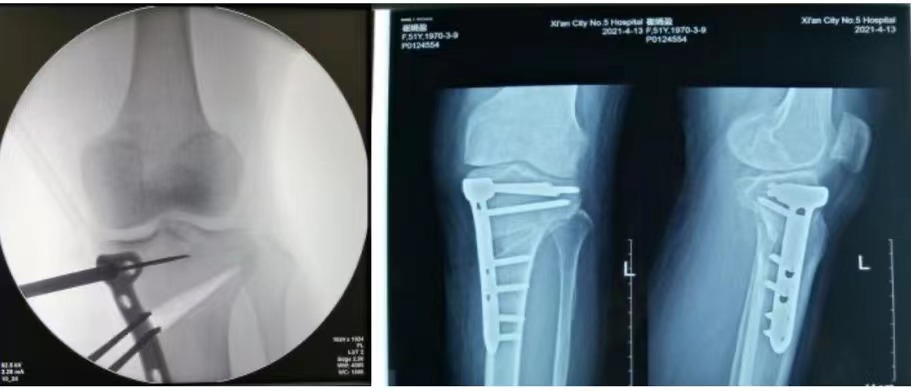

经过对患者影像学资料仔细分析及测量,精确设计截骨角度及纠正力线,完善术前检查,排除手术禁忌。手术由黄小强副院长主刀,鲁军伟、陈安强主治医师为助手,手术麻醉科医护的密切配合,按术前方案精准矫形,顺利完成手术。

术后,黄小强副院长例行查房,指导患者功能锻炼。术后第一天患者膝伸屈活动度均达正常,摄片示患肢力线已精准矫正到术前设计的角度,功能恢复很快,患者十分满意,于术后第4天顺利出院。